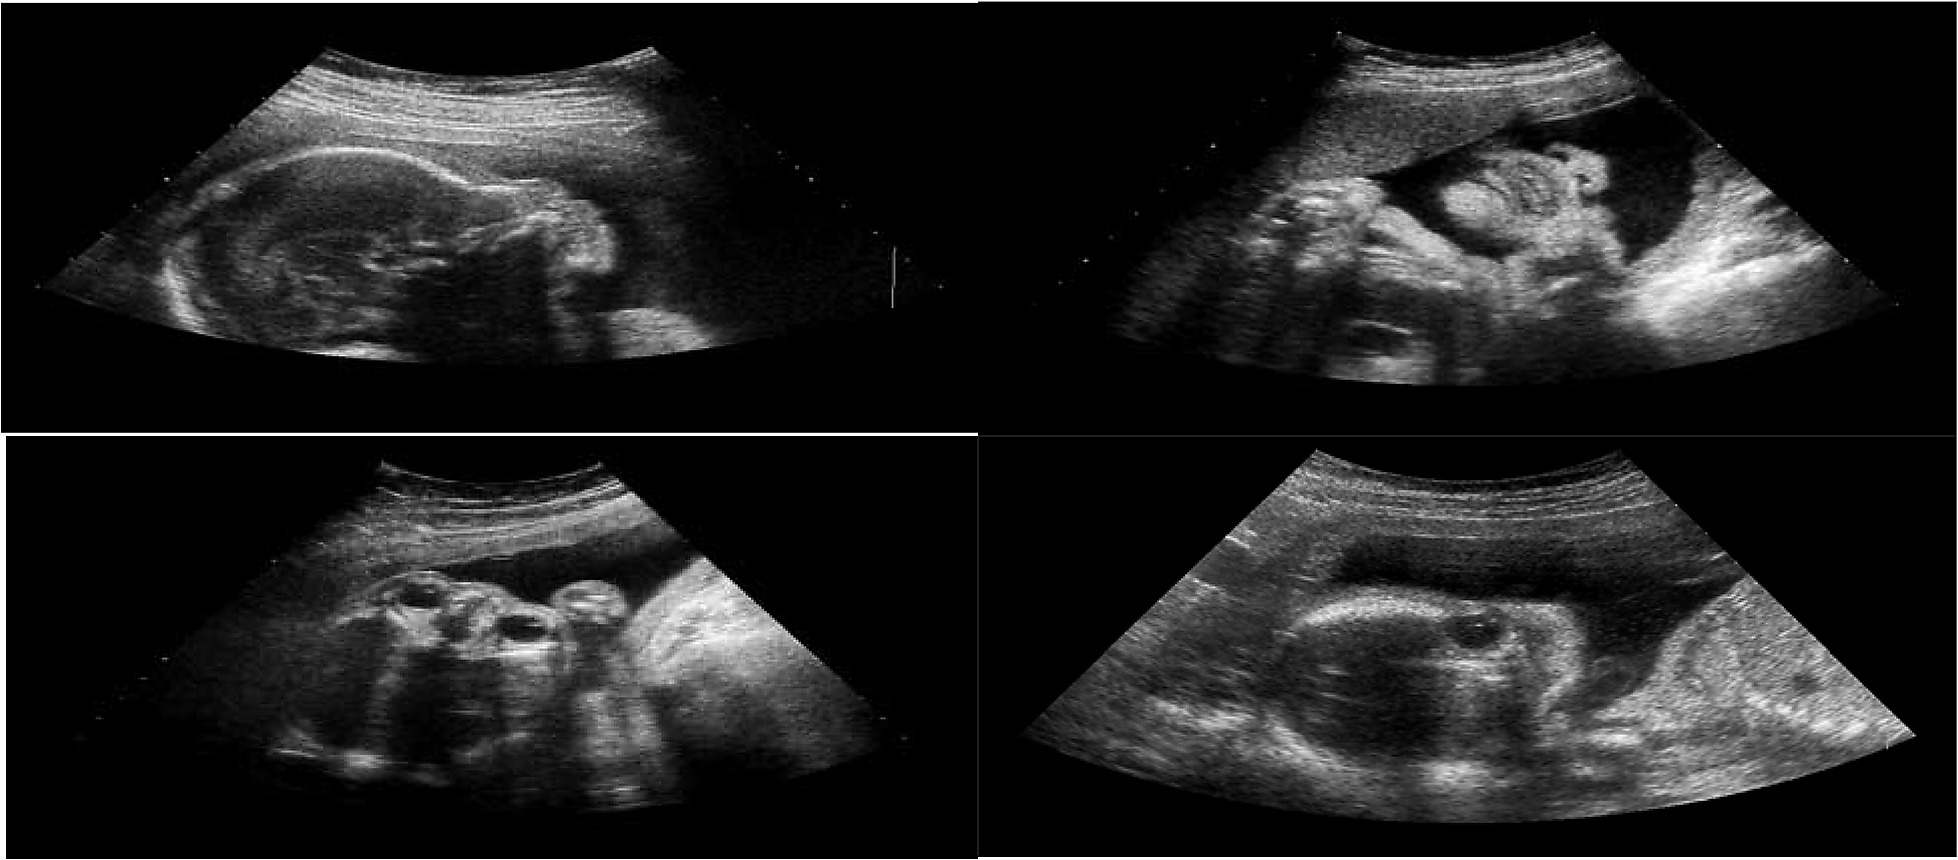

Siêu âm 4D là kỹ thuật chẩn đoán hình ảnh hiện đại nhất hiện nay trong lĩnh vực sản khoa. Khác với siêu âm 2D truyền thống chỉ cho hình ảnh đen trắng, hoặc 3D tĩnh, thì siêu âm 4D cho phép quan sát hình ảnh chuyển động thật thời của thai nhi trong bụng mẹ, dưới dạng hình ảnh màu sắc rõ nét, gần như video trực tiếp.

Mẹ bầu có thể nhìn thấy các cử động của con như:

Ngáp, mút tay

Cười, nhăn mặt, quay đầu

Đạp chân, cử động tay

Thậm chí là nhịp tim đập

1. Quan sát hình ảnh thai nhi sống động, sắc nét

Siêu âm 4D cho phép cha mẹ nhìn thấy khuôn mặt, cử động và biểu cảm của bé rõ ràng. Đây là trải nghiệm xúc động, giúp kết nối cảm xúc giữa cha mẹ và con từ trong bụng.

Nhiều mẹ chia sẻ rằng, lần đầu nhìn thấy bé nhăn mặt hay mỉm cười đã khiến họ rơi nước mắt vì xúc động.